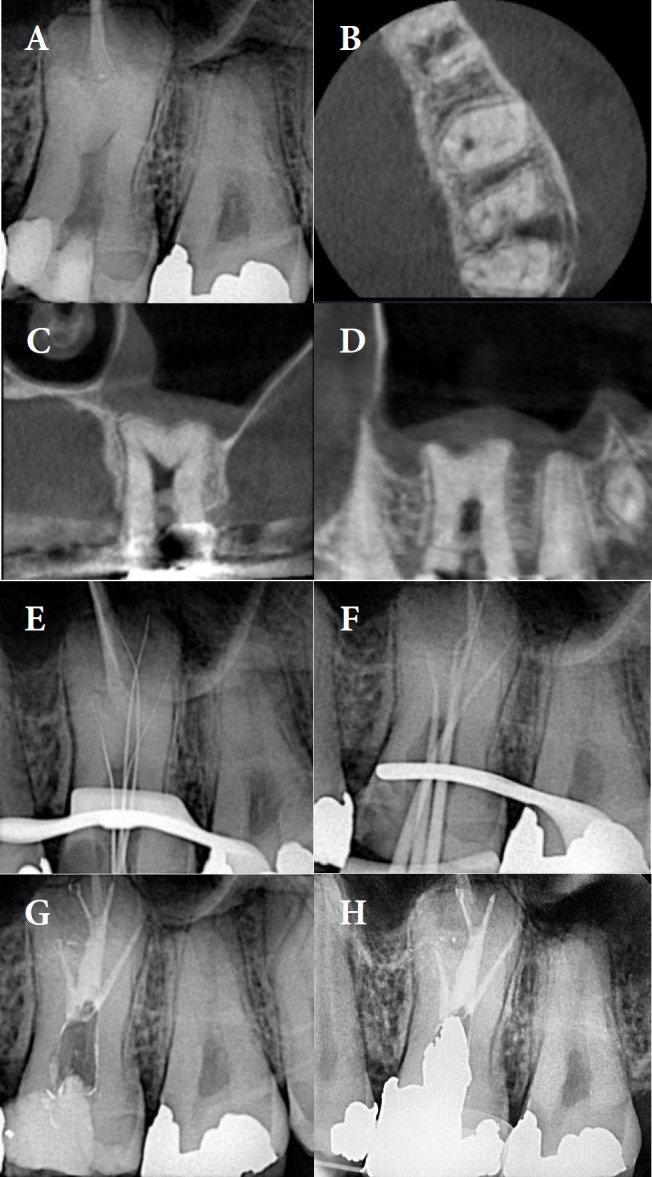

紧牙畸形是一种牙齿异常,其特征是在牙骨质-牙釉质交界处没有颈椎收缩,牙髓底顶端移位,牙髓腔扩大。由于其形态多变,根管孔深,根管系统复杂,因此对牙髓治疗提出了独特的挑战。本文报道了3例全身健康患者的高牛头牙症(牛头牙指数≈50),包括上颌第一磨牙、下颌第三磨牙和下颌第二前磨牙。锥束计算机断层扫描(CBCT)有助于诊断和治疗计划。根管治疗在牙科手术显微镜下进行,仔细探查,化学力学仪器使用旋转锉,5.25%次氯酸钠大量冲洗,温垂直封闭。12个月后,随访显示所有患者临床和影像学无症状,表明治疗成功。由于其解剖学的复杂性,剑齿虎症提出了重大的挑战。建议采用多方面的方法,包括CBCT、牙科手术显微镜、超声冲洗和温垂直封闭。这个系列的病例表明,先进的诊断辅助和细致的技术,甚至可以有效地管理高牛牙。

Taurodontism is a dental anomaly characterized by the absence of cervical constriction at the cemento-enamel junction, apical shifting of the pulpal floor, and an expanded pulp chamber. This condition presents unique challenges in endodontic diagnosis and treatment due to its variable morphology, deeply located orifices, and complex root canal system. This paper reports three cases of hypertaurodontism (Taurodont Index ≈ 50), including a maxillary first molar, mandibular third molar, and mandibular second premolar in systemically healthy patients. The identification and treatment planning were facilitated by cone-beam computed tomography (CBCT). Root canal therapy was performed under a dental operating microscope, with careful exploration, chemomechanical instrumentation using rotary files, copious irrigation with 5.25% sodium hypochlorite, and warm vertical obturation. Twelve months later, follow-up visits showed that all patients were clinically and radiographically asymptomatic, indicating successful outcomes. Taurodontism presents significant challenges due to its anatomical complexities. A multifaceted approach involving CBCT, dental operating microscopes, ultrasonic irrigation, and warm vertical obturation is recommended. This case series demonstrates that with advanced diagnostic aids and meticulous techniques, even hypertaurodontic teeth can be effectively managed.